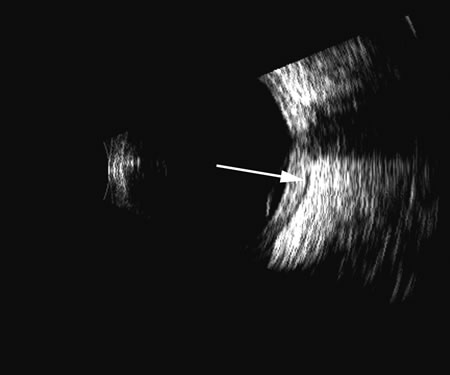

Fig. 4. A clinically well-placed posterior chamber intraocular lens nevertheless had patient complaints of photophobia and irritation due to a folded haptic (arrow).

Fig. 5. An anterior chamber intraocular lens has had the support haptics dislocate posterior to the iris plane and can be seen as typical foreign body echogenic reflections (arrows).